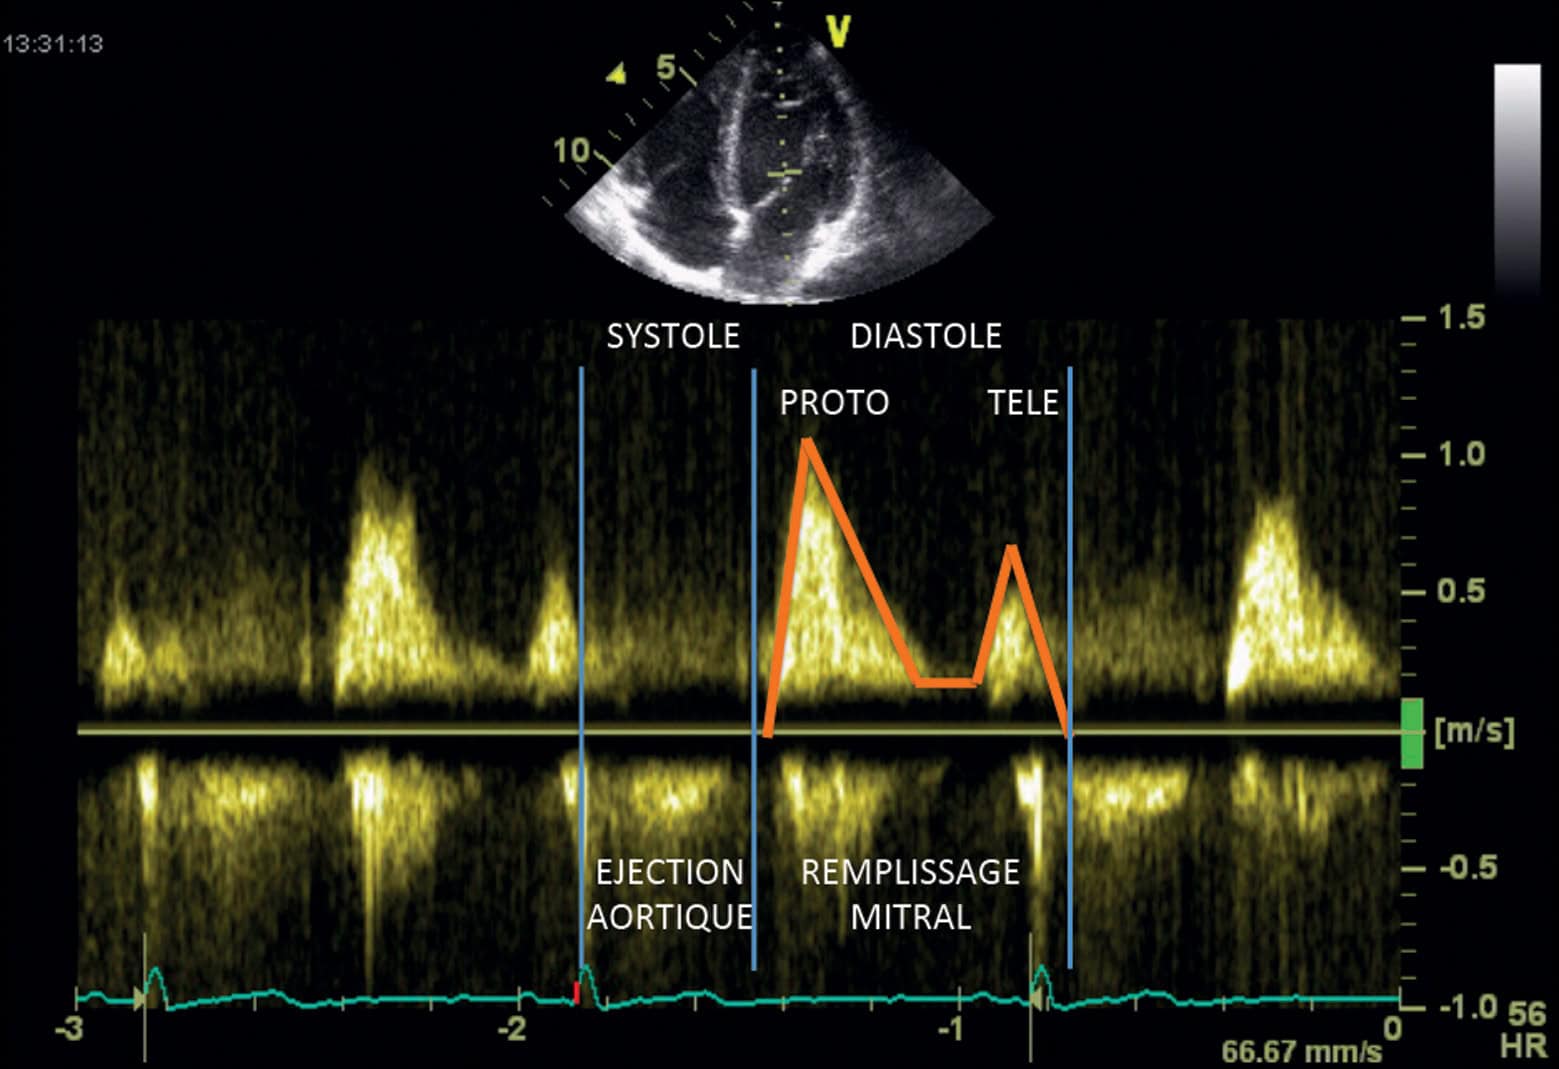

Pour comprendre les différents types de galop, il faut connaître les différents temps du remplissage ventriculaire (voir chapitre 1, Physiologie, Cœur). Pour cela, l’analyse Doppler du flux mitral (ou flux de remplissage ventriculaire gauche) mesuré à l’écho-Doppler cardiaque est particulièrement utile (fig. 5.10). Cette analyse permet de mesurer les vitesses d’écoulement du sang de l’atrium (en pratique la vitesse de déplacement des hématies) vers le ventricule gauche au niveau d’une zone d’échantillonnage placée au sommet des feuillets mitraux. La figure montre les trois temps du remplissage ventriculaire :

- le premier temps correspond au début de la diastole (appelé remplissage ventriculaire rapide), qui est essentiellement déterminée par la différence de pression entre atrium gauche et ventricule gauche, associé à un phénomène d’aspiration par le ventricule, qui se traduit en Doppler par une onde positive (le flux se dirige vers le capteur) ;

- puis les pressions entre les deux cavités s’équilibrent, le phénomène de succion du ventricule s’atténue : c’est la période de diastasis ;

- puis intervient la contraction de l’atrium, qui provoque une chasse sanguine en fin de diastole (télédiastole) vers le ventricule.

Les différents bruits de galop sont synchrones de ces différents flux :

- le galop protodiastolique (B3), indépendant de la contraction de l’atrium, est lié au remplissage rapide ; il est toujours présent en fibrillation atriale ;

- le galop télédiastolique (B4) n’est présent qu’en rythme sinusal car il est généré par la chasse sanguine dépendante de la contraction de l’atrium ;

- le galop de sommation correspond à la fusion des temps proto- et télédiastoliques et n’est retrouvé qu’en rythme sinusal.

Figure 5.10. Tracé Doppler mitral.

L’enregistrement du flux transmitral en Doppler pulsé renseigne sur la part respective du remplissage rapide (PROTO) et de la contraction atriale (TELE), ainsi que sur la qualité de la relaxation VG.